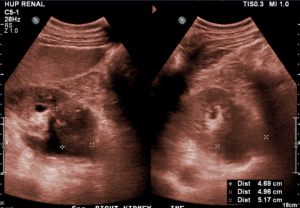

A previously healthy 67-year-old male presented to the emergency department after 4 days of bilateral flank pain consistent with kidney colic. The pain was associated with dysuria, fevers, urinary hesitancy, and frequency. He was afebrile and hemodynamically stable on initial presentation. Physical exam was significant for lower abdominal and left costovertebral angle tenderness. Relevant labs showed a leukocytosis of 22,000 cell/µL with 13% bands and creatinine of 2.61 mg/dL without a known prior baseline. Urinalysis was positive for pyuria, blood, and nitrite. The patient received broad-spectrum antibiotics and was admitted for presumed acute kidney injury secondary to pyelonephritis. The admitting resident team performed POCUS evaluation of the kidneys and found an anechoic collection bilaterally within the kidney sinus along with dilated calyces (Figure 1). Additional color flow Doppler was applied to the anechoic space and confirmed the absence of a vascular component. These findings supported the determination that kidney injury was likely multifactorial due to obstructive nephropathy in addition to pyelonephritis. A Foley catheter was placed immediately for bladder decompression. Comprehensive kidney and bladder ultrasonography was performed by radiology within 2 hours of POCUS exam. This confirmed severe bilateral hydronephrosis as well as mobile echogenic debris and thickened bladder wall suggestive of cystitis. Left kidney size was 12.8 cm and right kidney size was 14.3 cm. Post-void residual bladder volume was ~400 ml and enlarged prostate was visualized. Urology was consulted and the patient required bilateral ureteral stent placement. The most likely diagnosis was pyelonephritis complicated by hydronephrosis secondary to enlarged benign prostatic hyperplasia. The patient’s clinical symptoms markedly improved and creatinine improved to 2.46 mg/dL. He was discharged with oral antibiotics and outpatient urology follow-up.

Figure 1. POCUS evaluation in acute kidney injury. Image A. With the patient supine, place a low-frequency probe (probe marker pointing cephalad) at the mid-axillary line (dotted line) just above the costal margin, with the ultrasound beam directed into retroperitoneal space. The longitudinal l view of the kidney should be in view. The probe should then be rotated clockwise 90 degrees to obtain the transverse view (image not shown). Image B. Representative image of normal right kidney in the longitudinal view with structures labeled. Note the normal kidney architecture with the non-dilated kidney pelvis and preserved kidney parenchyma (cortex, pyramids). Image C. Representative image of hydronephrosis of the right kidney in the longitudinal view with structures labeled. Note the abnormality within the urinary collecting system including the central dilation of the kidney pelvis (anechoic) and calices which appear anechoic within the hypoechoic narrowed kidney cortex.